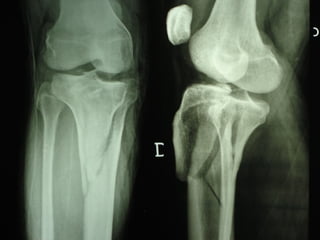

Dal Gennaio 2000 al Dicembre 2005 27 placche LISS di femore

Stabilità tramite attrito placca    osso

Osso porotico Stabilità con viti autobloccate

INDICAZIONI COMUNI Fratture sovracondiloidee Fratture intercondiliodee Fratture diafisarie distali PARTICOLARI Fratture con grave osteoporosi Fratture periprotesiche